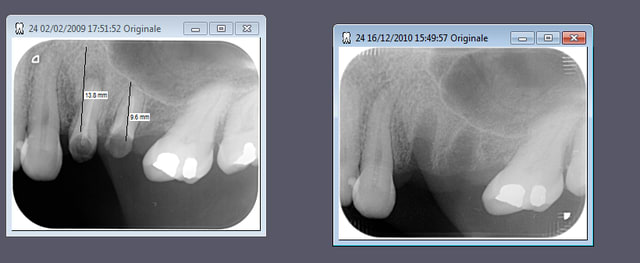

deux axiom en 24 25

dans l'ordre

avulsion des dents et j'ai tracté tout le vestibule en palatin et suturé sur le bord palatin sans membrane sans matériau de comblement

pose de deux axiom en 14 15 mais... plus de GA en vestibulaire puisque tout est sur la crête

à la mise des vis de cicat incision palatine en 1/2 épaisseur puis pleine épaisseur sur le bord vestibulaire de la crête et décharge mésiale et distale et on redéplace tout en vestibulaire petites incision (à la chez plus ki) et sutures.

pas mécontent du modelage en vestibulaire et de la "papille" interimplantaire. on verra à la maturation ce que ça devient.

au passage amusant de voir que si on se contente de regarder les radios n se dit fouilla t'était bourré le jour de la pose t'es à des kilomètres de la 6 (en fait 7 mésialée)

je suis pas satisfait de ma décharge mésiale noah je sais...